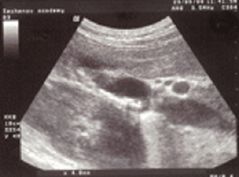

Что показывает холестероз на УЗИ: диагностика и лечение